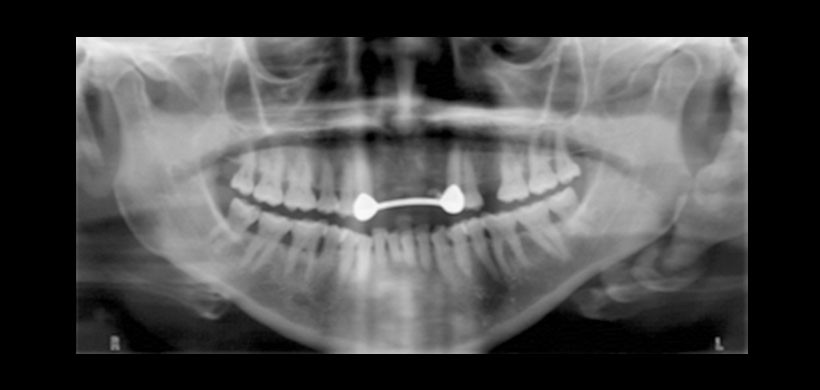

Se han utilizado múltiples modalidades de estudio imagenológico para confirmar el diagnóstico clínico, incluyendo las radiografías lateral de cuello y anteroposterior de cráneo, panorármica, la tomografia computarizada de haz cónico (TCHC) y la tomografía espiral multicorte (TEM) La técnica de elección para el diagnóstico y evaluación del síndrome de Eagle es el TEM con reconstrucción 3D. Permite obtener información del tamaño, dirección y relación del complejo estiloideo con las estructuras vasculonerviosas cercanas

Figura 1. Radiografía panorámica, es el examen de imagen de mayor uso y en el cual se realiza la primera evidencia de la mineralización se los procesos estilohioideos.